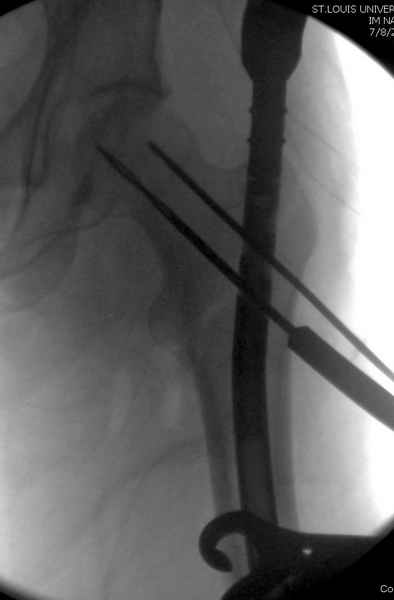

Как раз недавно у меня был примерный случай: больному 36 лет, поступил ночью, травма в результате мотоциклетной аварии, кроме чрезвертельного и спирального перелома левого бедра имеется переломы костей предплечья с этой же стороны. Скелетное вытяжение, а на следующий день больной про оперирован на ортопедическом столе с дистракцией. Чтобы не расколоть чрезвертельный перелом провели временную спицу ближе к переднему кортексу, из малого разреза костодержатель для репозиции, а фиксацию провели антиградным штифтом. Этапы операции на снимках.